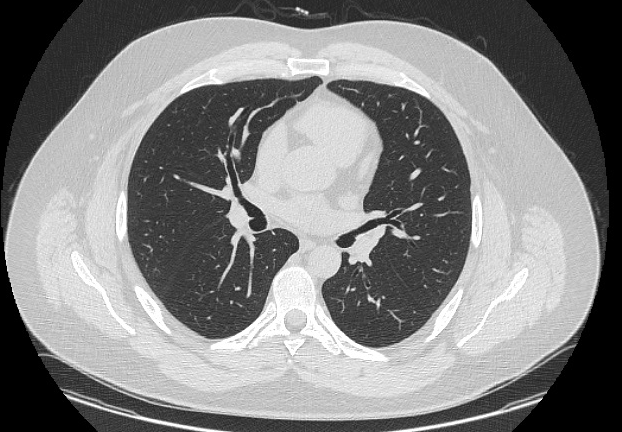

New here, got a bit of fun for you for those who are interested (this is not homework) - take a look at the images attached.

One is a smoker with diagnosed COPD, a small centrilobular lesion is indicated by the white arrow.

The other two are mine, from an MRI scan I had done to investigate a chronic cough, radiologist says my lungs are 'clear'... but I think it looks eerily similar to the COPD example.

1. These are CT images.

2. The white arrow is pointing to a bronchus, a normal anatomic structure. It would be very odd for you to not have bronchi.

3. The example "smoker" may have bronchitis, but there's no real signs of emphysema on the image you showed us.

4. As stated previously, the provided images provided from your lungs look clear.